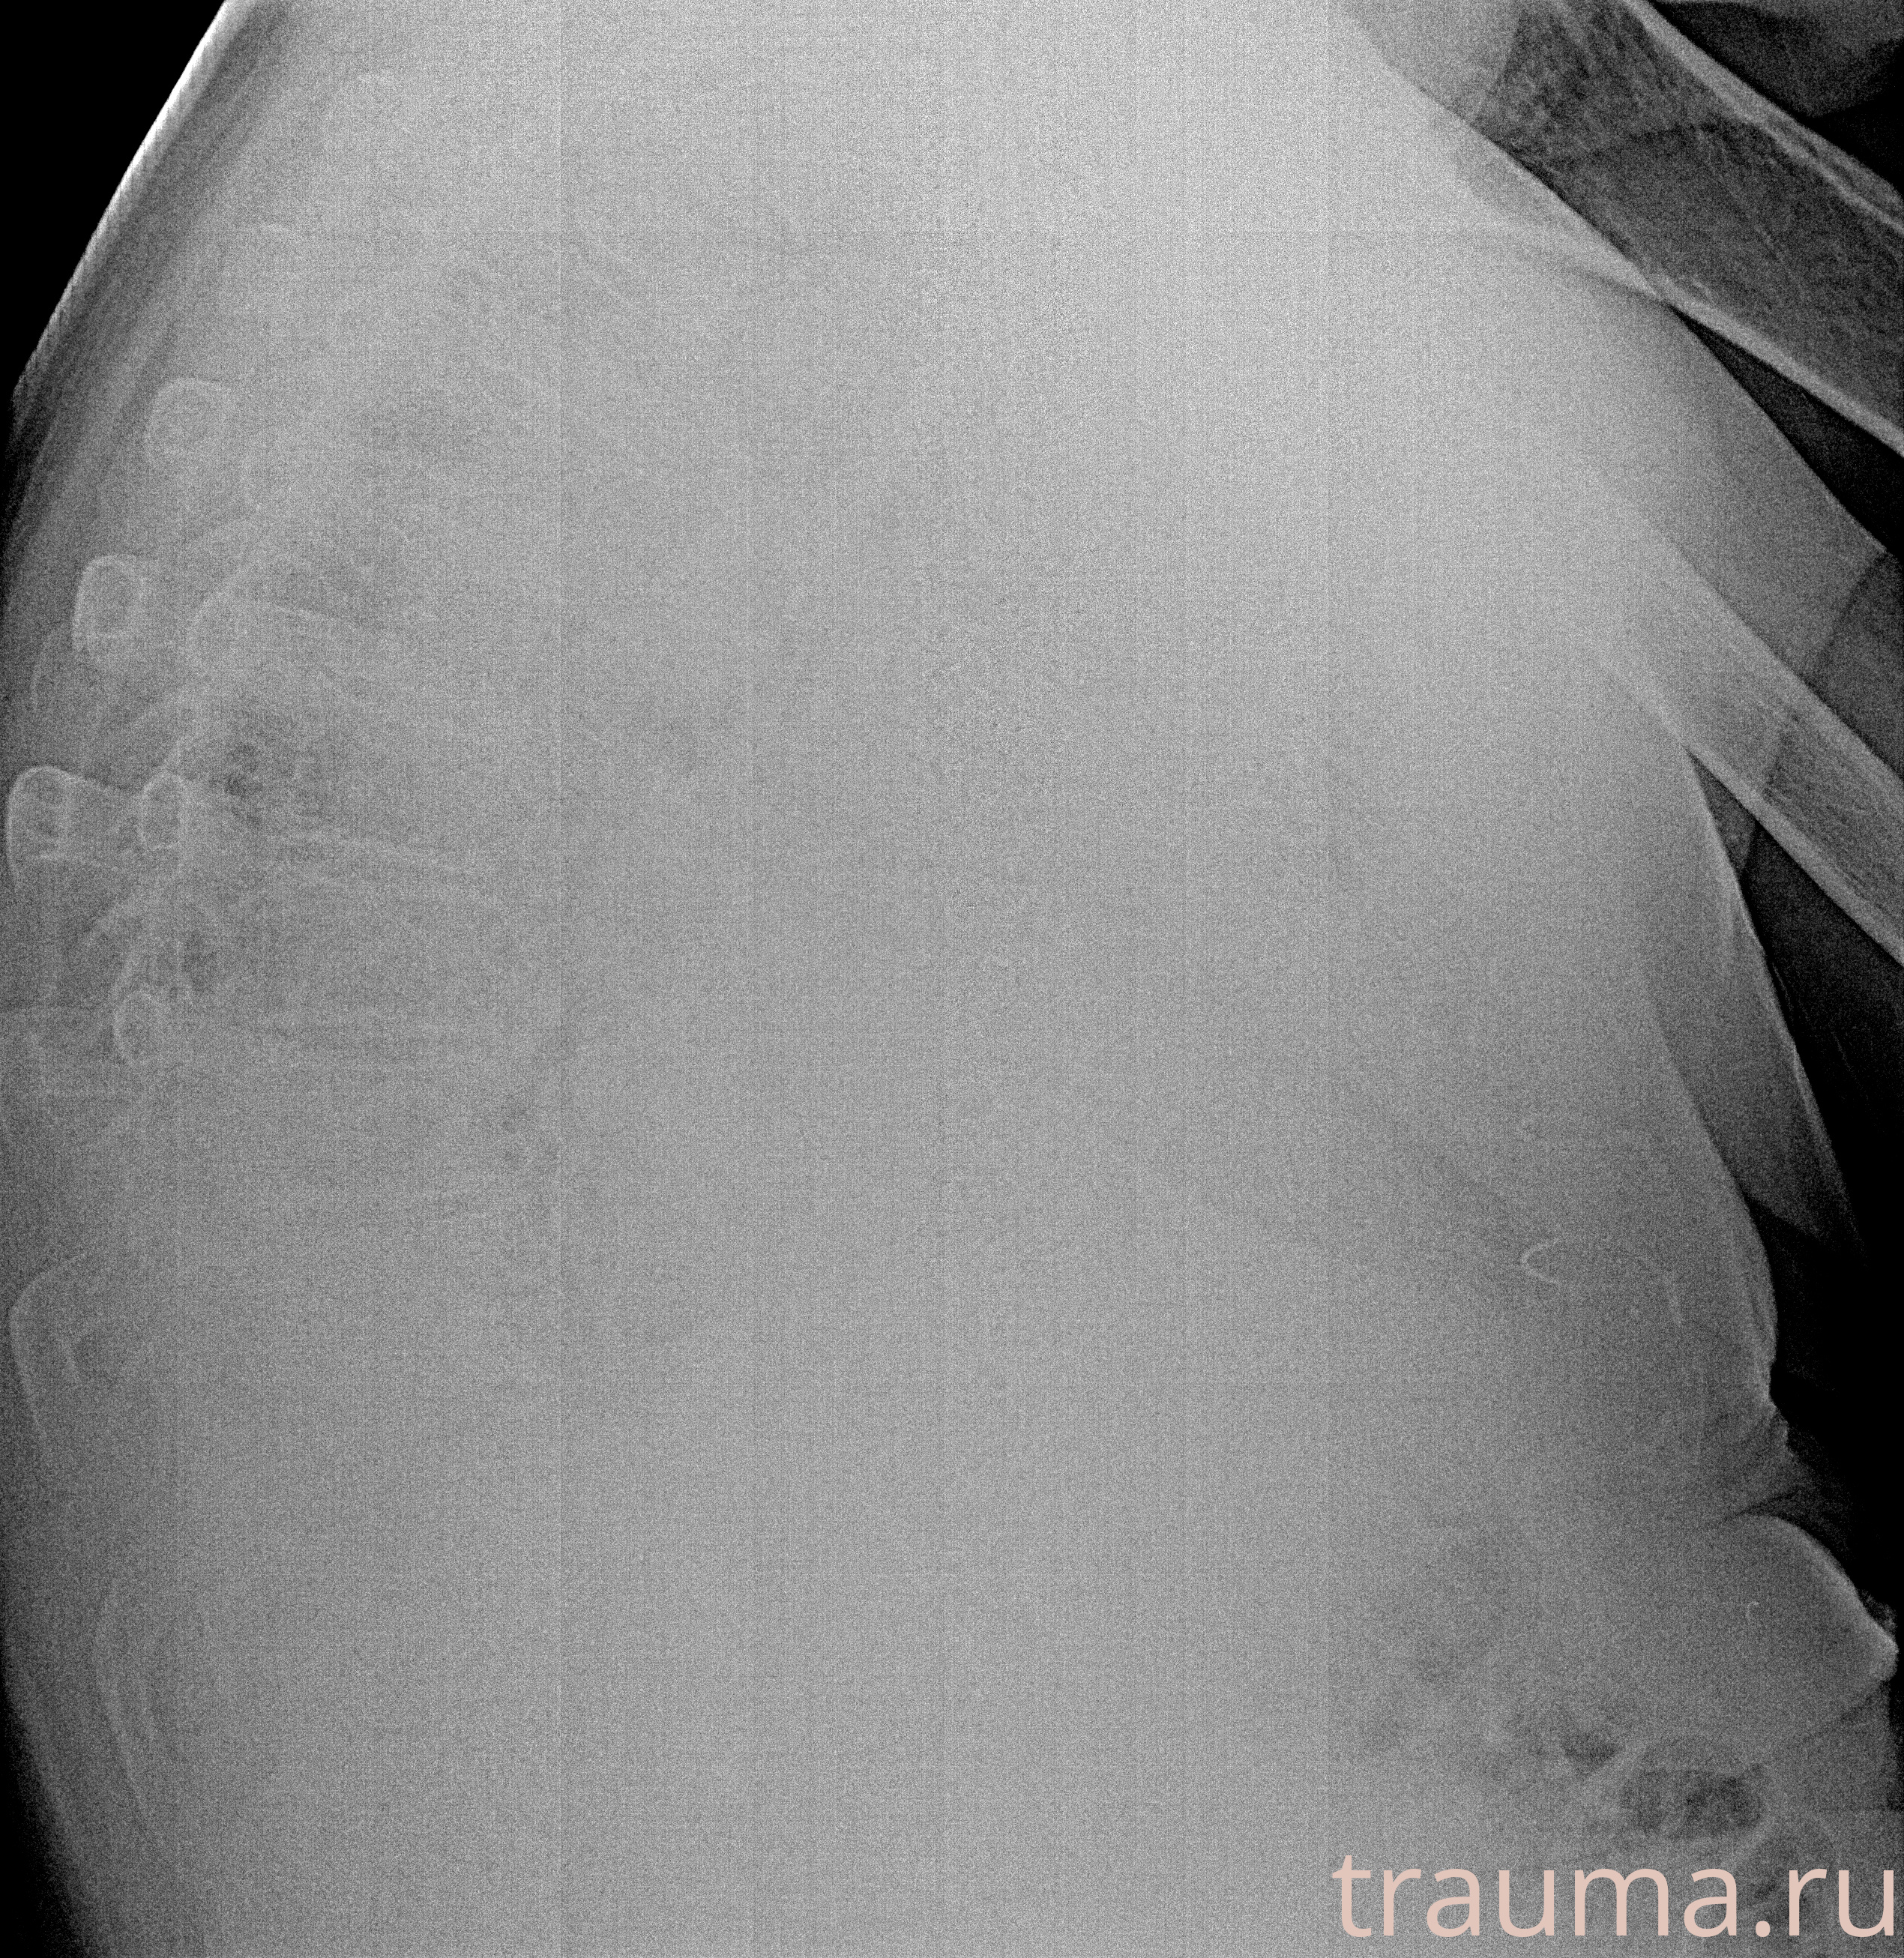

Рентген на дому: по вашему адресу приезжает врач-рентгенолог, травматолог-ортопед с мобильным рентгеновским аппаратом, проводит диагностику травмы или заболевания, делает необходимые рентгенограммы, дает рекомендации по дальнейшему лечению. Получить качественные снимки в домашних условиях возможно благодаря уникальной методике, разработанной МосРентген Центром для института  Склифосовского